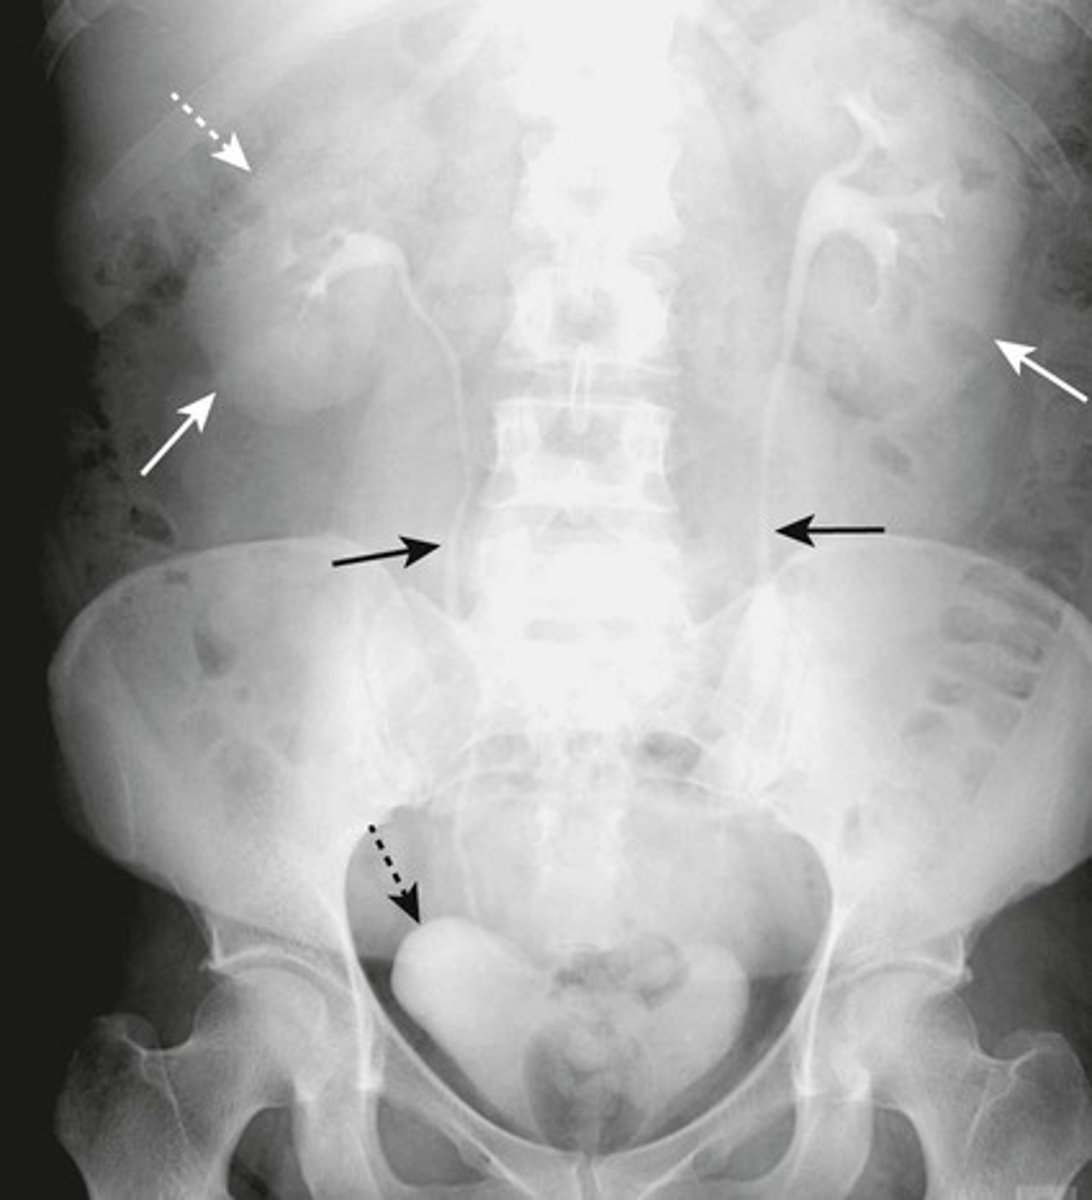

HEPATOMEGALY

BLACK ARROWS: displacement of all bowel loops from RUQ to iliac crest and across the midline.

Hepatomegaly is usually indicated by displacement of all bowel loops from RUQ to the iliac crest and across the midline, as in this pt with cirrhosis.

Sometimes the liver can be so enlarged that it will be obvious even on conventional radiographs

SPLENOMEGALY

WHITE ARROWS: spleen

BLACK ARROW: 12th posterior rib

Spleen is usually about 12 cm in length and DOES NOT project below the 12th posterior rib.

Splenomegaly can also displace the stomach bubble toward or across the midline.